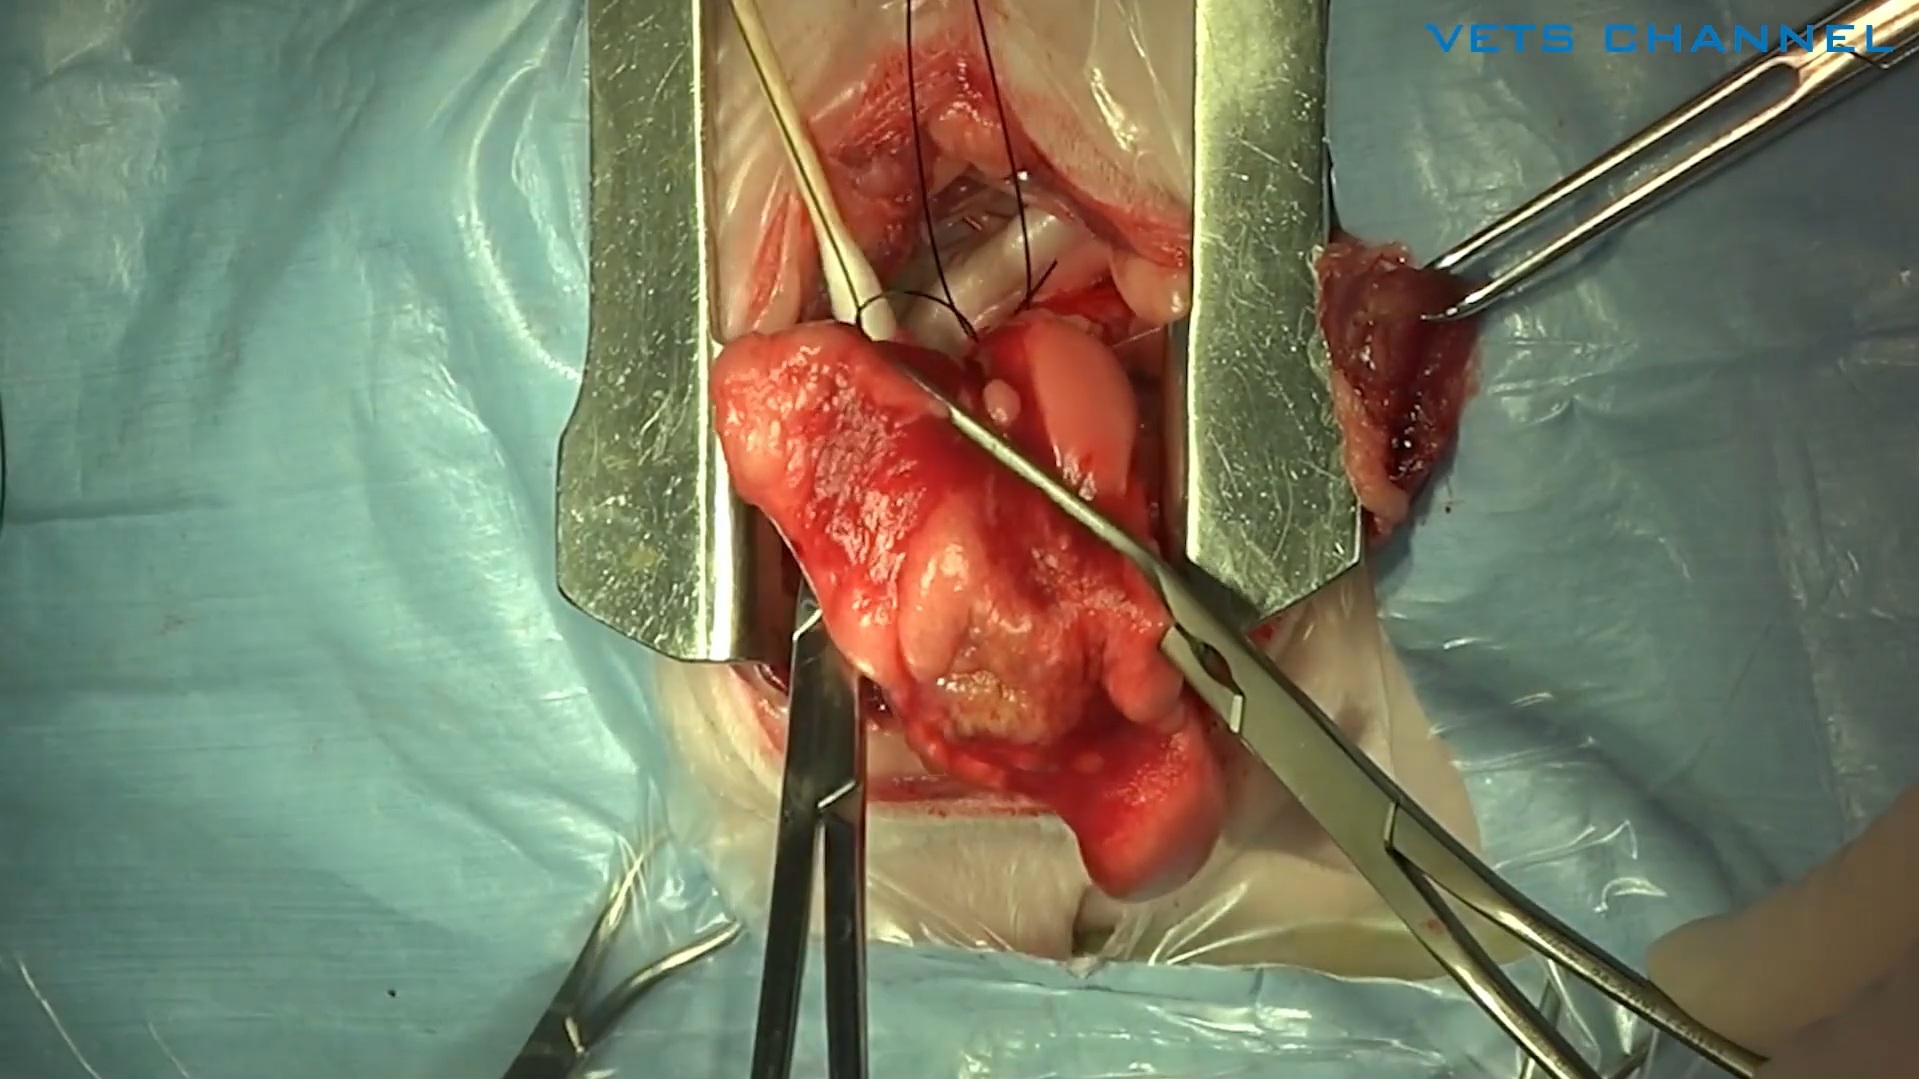

腫瘍に対する腸管切除および吻合術

- OPE

- 軟部外科

- 消化器科

- 猫

上原 拓也先生(小滝橋動物病院 目白通り高度医療センター)

59分

2025/10/31

腫瘍に対する腸管切除および吻合術

- OPE

- 軟部外科

- 消化器科

- 猫

上原 拓也先生(小滝橋動物病院 目白通り高度医療センター)

59分

2025/10/31